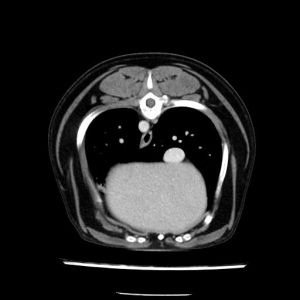

La lesione focale epatica , la ceus,la Tac e il chirurgo .